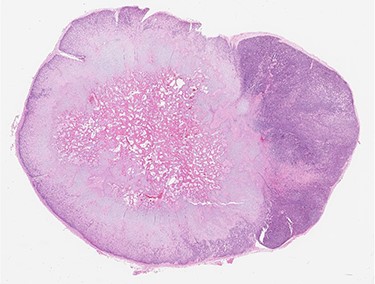

Low-power view of the lesion showing central ossification (H&E).